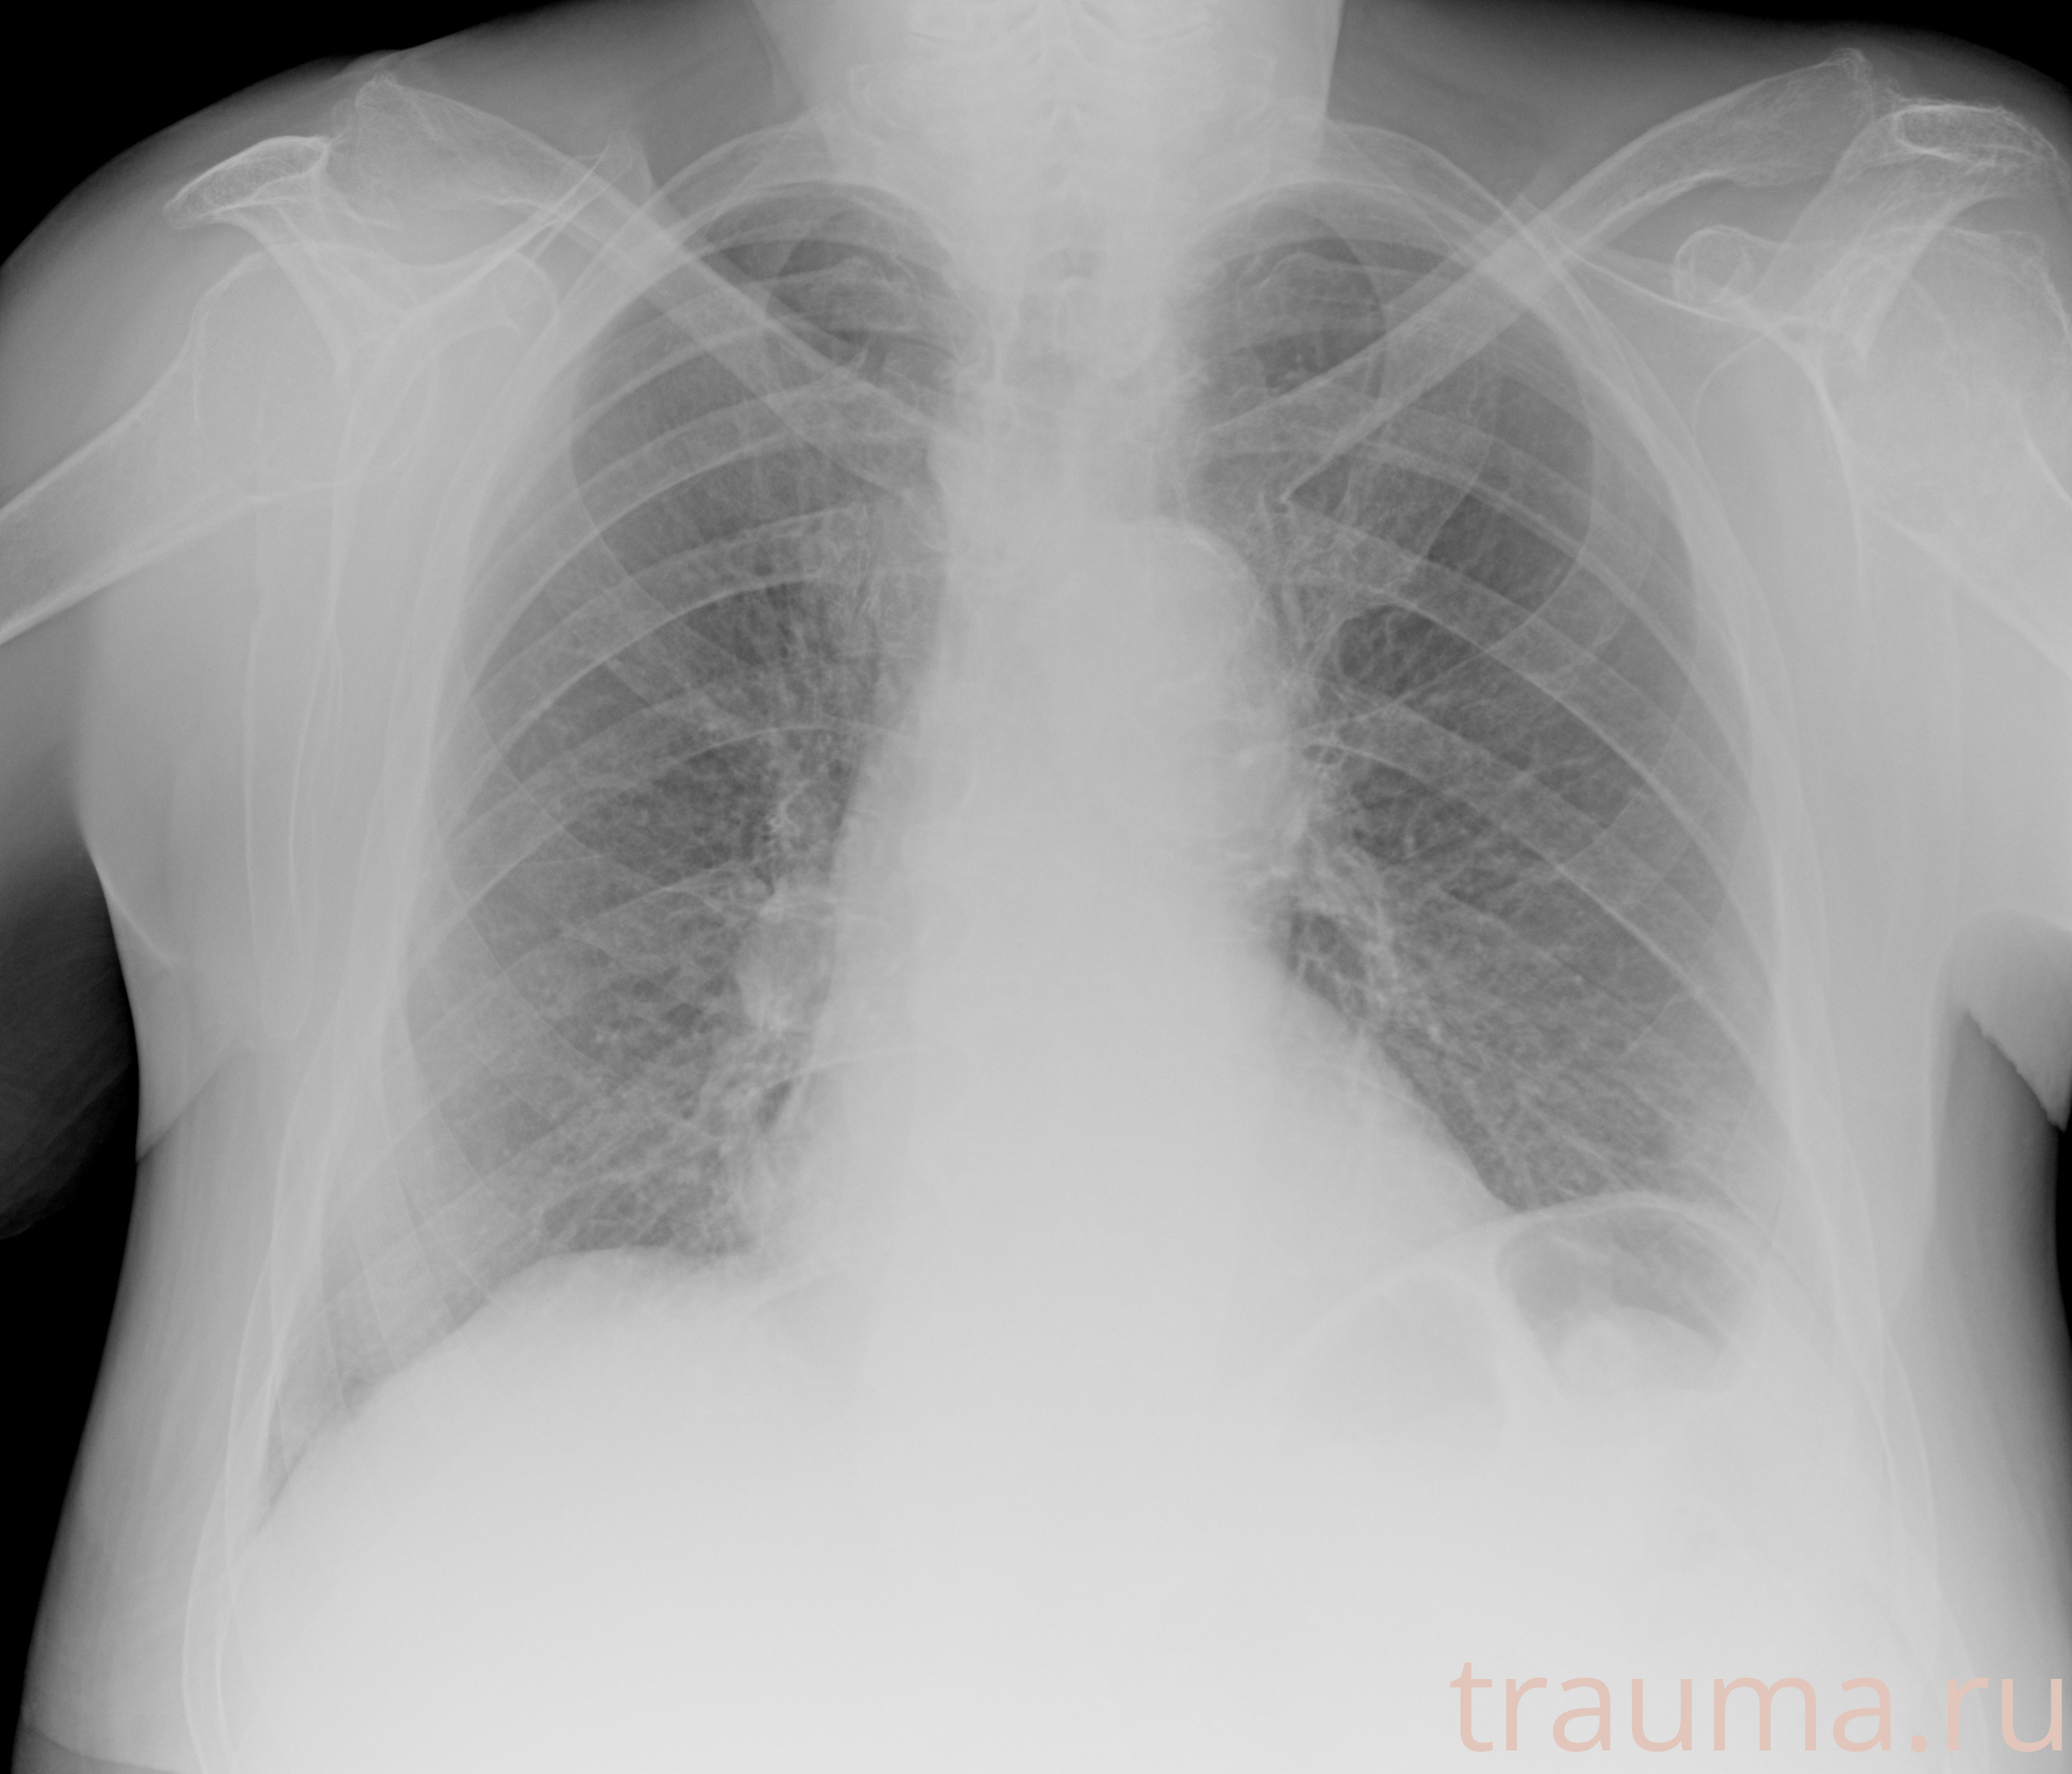

Рентгенограммы

Рентген на дому: по вашему адресу приезжает врач-рентгенолог, травматолог-ортопед с мобильным рентгеновским аппаратом, проводит диагностику травмы или заболевания, делает необходимые рентгенограммы, дает рекомендации по дальнейшему лечению. Получить качественные снимки в домашних условиях возможно благодаря уникальной методике, разработанной МосРентген Центром для института  Склифосовского

при переломе шейки бедра и пневмонии от компании МосРентген Центр - партнера Института имени Склифосовского